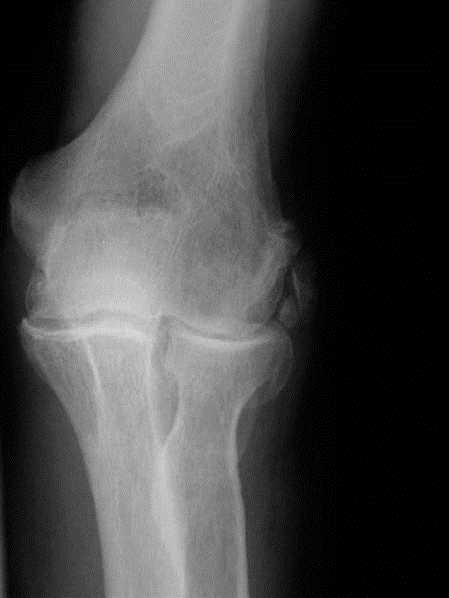

Elbow structured oral examination question 4 EXAMINER : Good morning. Here are the radiographs of a righthand…

Elbow structured oral examination question 5 EXAMINER : I have a problem with my left elbow. Proceed. CANDIDA…

Elbow structured oral examination question 2 EXAMINER : Look at these radiographs of of the right elbow of a …